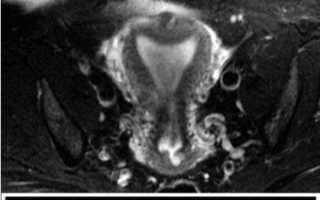

МРТ. Магнитно-резонансная томография — современный метод, который позволяет оценить не только анатомию органа, но и выявить сопутствующие заболевания и новообразования, если они имеются.